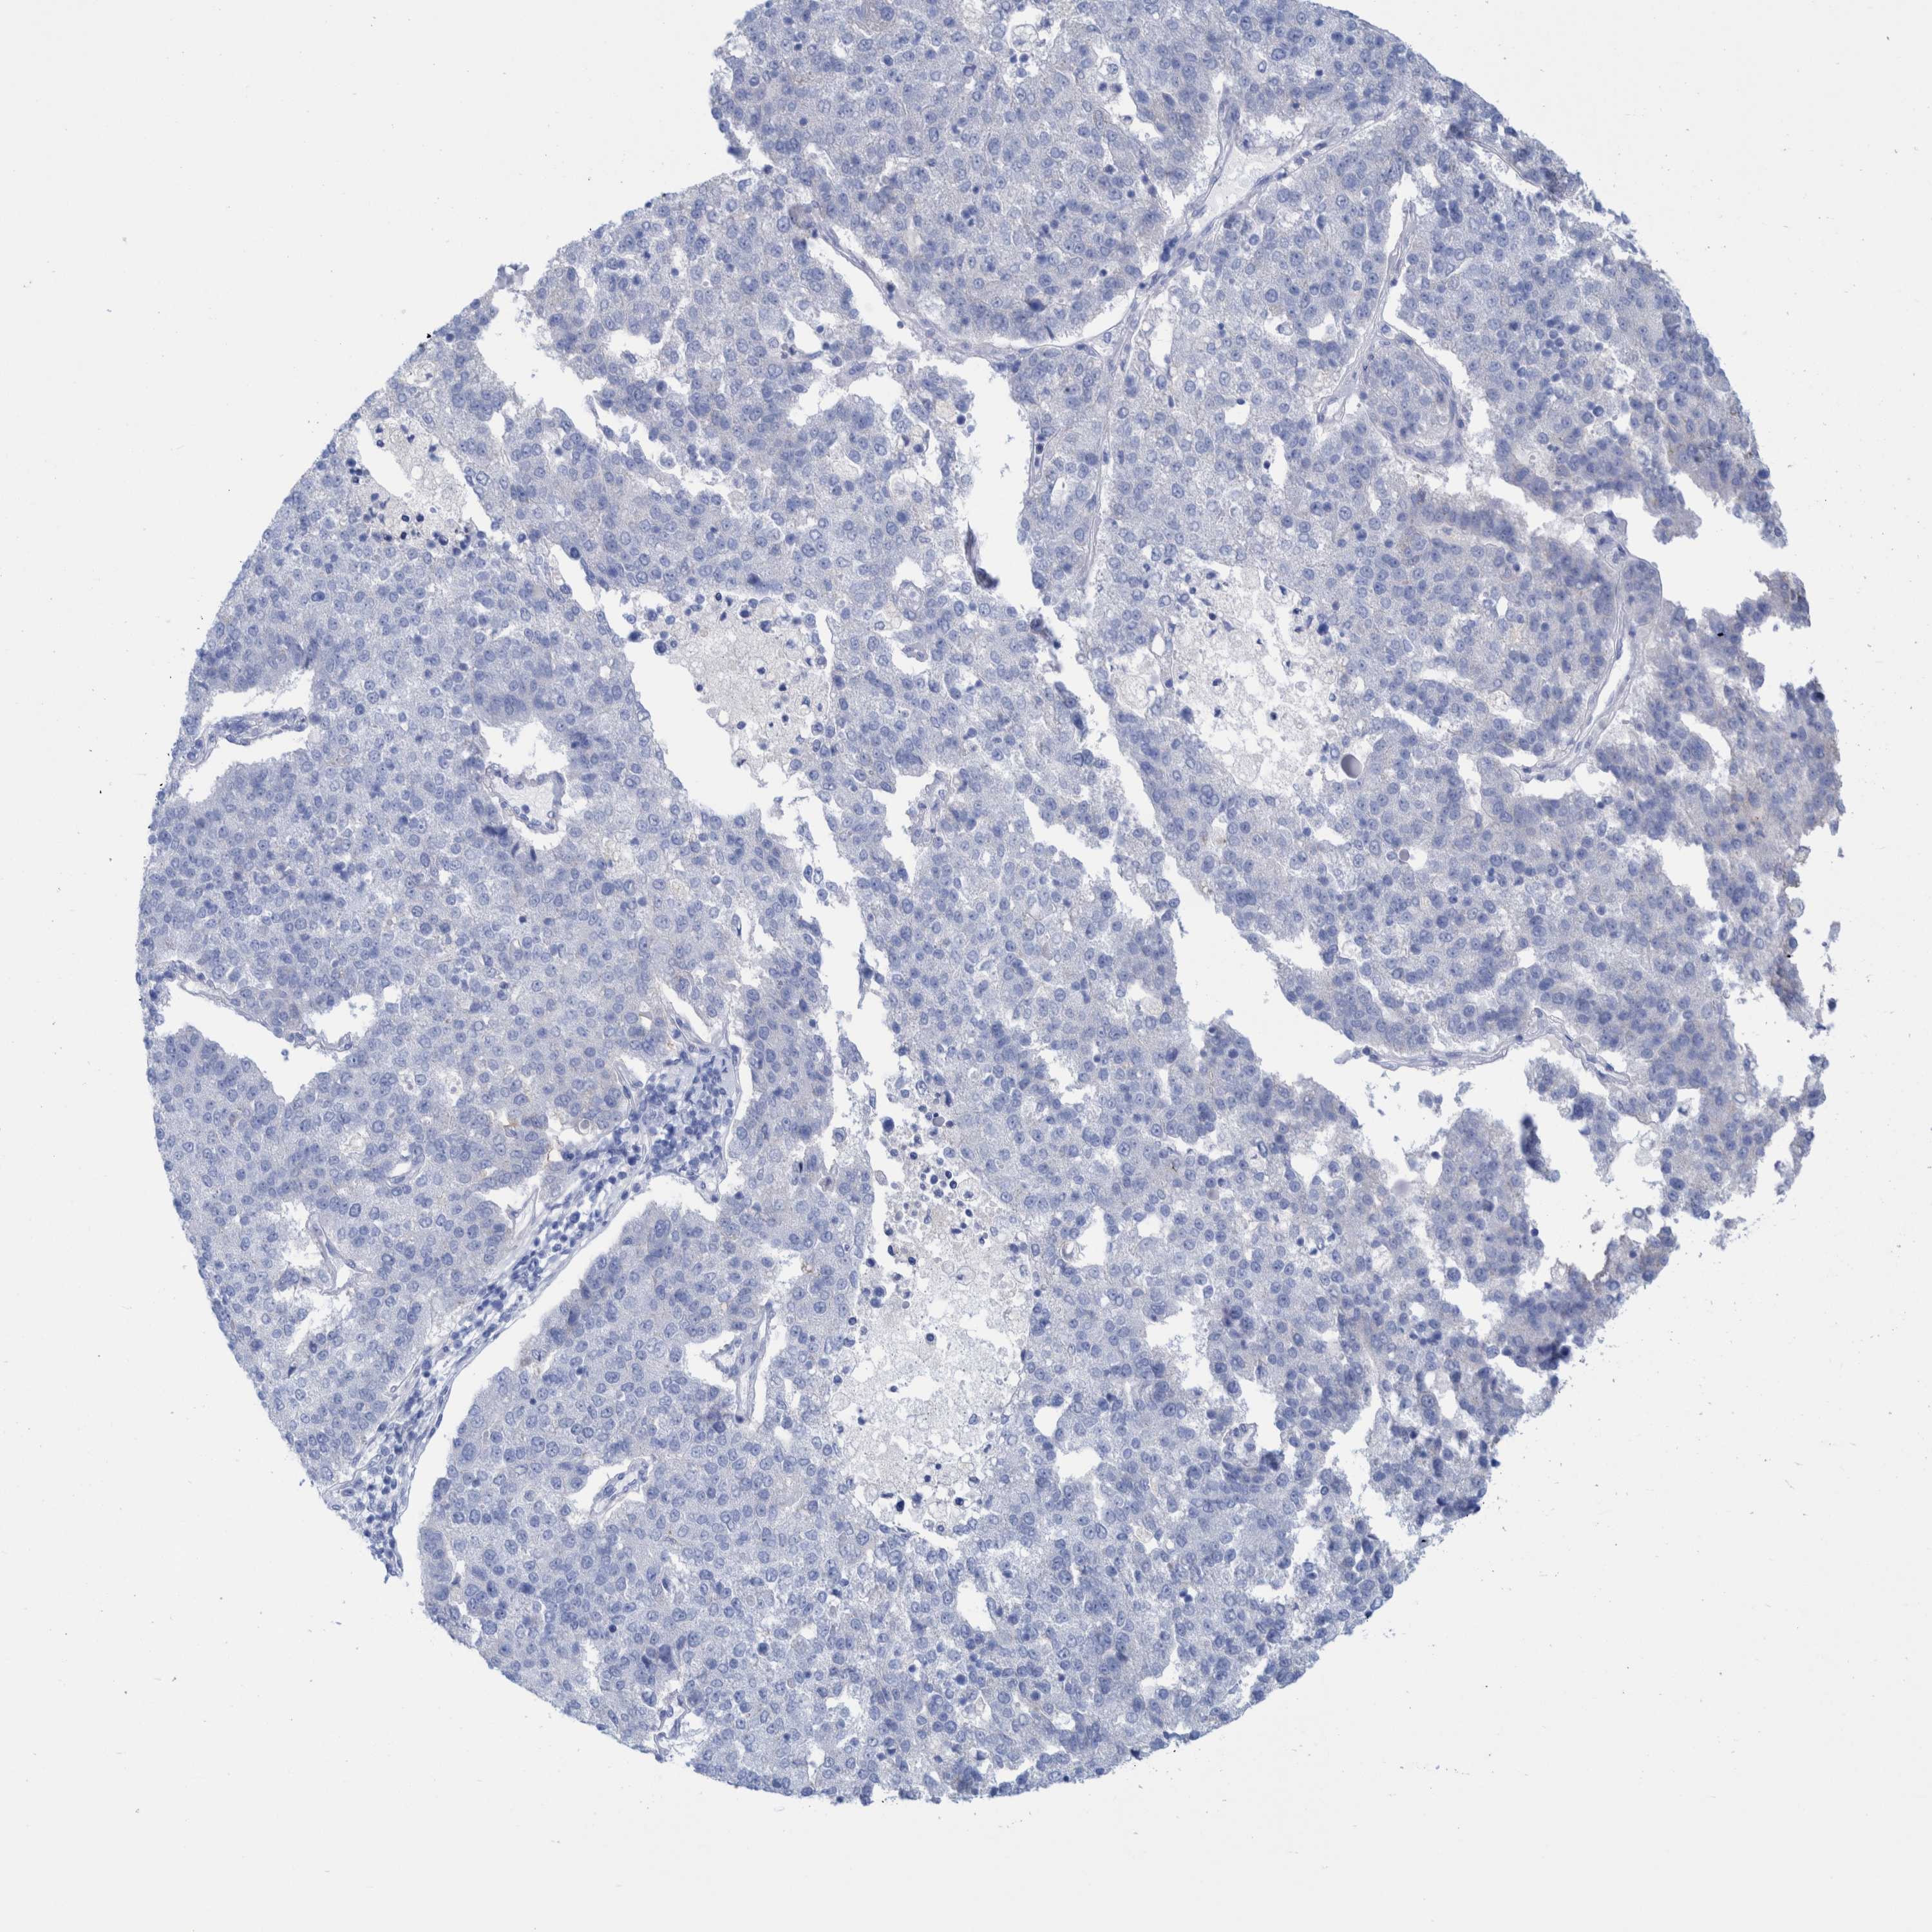

PANCREATIC CANCER - Protein expressioni

A mouse-over function shows sample information and annotation data. Click on an image to view it in a full screen mode. Samples can be filtered based on level of antibody staining by selecting one or several of the following categories: high, medium, low and not detected. The assay and annotation is described here.

Note that samples used for immunohistochemistry by the Human Protein Atlas do not correspond to samples in the TCGA dataset.

Antibody stainingi

Antibody staining in the annotated cell types in the current human tissue is reported as not detected, low, medium, or high, based on conventional immunohistochemistry profiling in selected tissues. This score is based on the combination of the staining intensity and fraction of stained cells.

Each image is clickable and will lead to virtual microscopy that enables deeper exploration of all samples and also displays staining intensity scores, fraction scores and subcellular localization as well as patient and tissue information for each sample.

Antibody HPA022269

Staining

High

Medium

Low

Not detected

Intensity

Strong

Moderate

Weak

Negative

Quantity

>75%

75%-25%

<25%

None

Location

Nuclear

Cytoplasmic/membranous

Cytoplasmic/membranous,nuclear

Adenocarcinoma, NOS